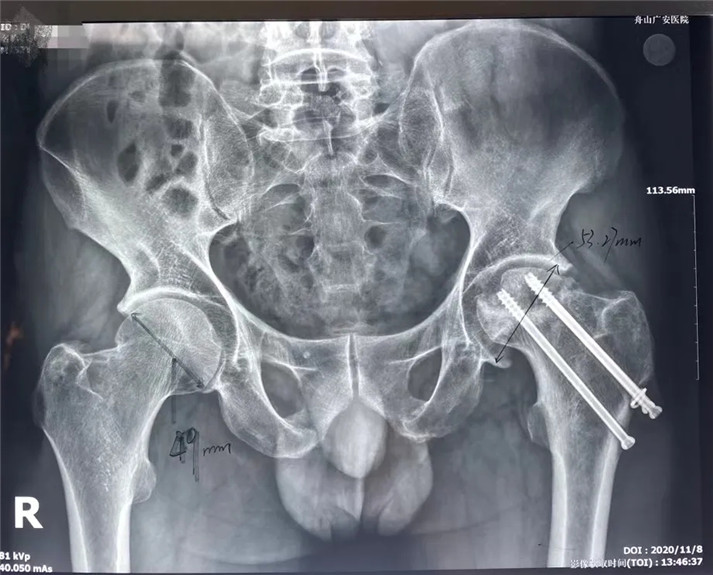

結(jié)合影像學(xué)表現(xiàn)研究后,骨科中心羅軍主任診斷丁先生為左股骨頭壞死,并建議其行全髖關(guān)節(jié)置換手術(shù)。

術(shù)前

考慮到患者的年齡、骨折類(lèi)型等情況,以及患者的種種擔(dān)憂(yōu),為精準(zhǔn)治療、加快愈合、避免關(guān)節(jié)脫位及肢體長(zhǎng)短不等,羅軍主任團(tuán)隊(duì)采用了近期引進(jìn)的AI HIP置換術(shù)前規(guī)劃系統(tǒng)為患者行術(shù)前規(guī)劃。他們將丁先生的術(shù)前CT數(shù)據(jù)導(dǎo)入到系統(tǒng)中,通過(guò)自動(dòng)識(shí)別骨盆和股骨建立了計(jì)算機(jī)數(shù)字三維模型。AI HIP顯示患者適合使用合適的髖臼杯、股骨柄、標(biāo)準(zhǔn)陶瓷球頭、陶瓷內(nèi)襯,并精準(zhǔn)定位了截骨線(xiàn),可以有效幫助醫(yī)生在手術(shù)中做到精確截骨。